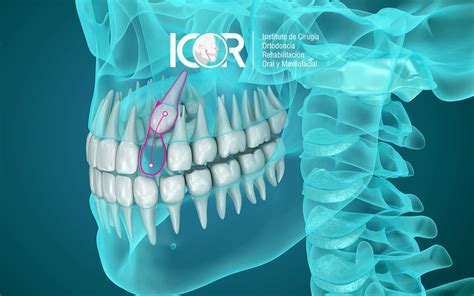

Los caninos retenidos, también conocidos como caninos incluidos, son dientes que no han erupcionado correctamente y permanecen atrapados en el hueso maxilar o la encía. Esta situación puede tener un impacto en la mordida y en la estética de la sonrisa.

Esta retención puede ser intraósea (cubierto por hueso) o submucosa (cubierto por encía). Es más común en el canino superior que en el inferior.

Si no se tracciona ortodóncicamente o se extrae un canino retenido, pueden surgir complicaciones graves, como infecciones locales, del seno maxilar o de la fosa nasal. Un diente retenido en una posición inadecuada puede causar diversas alteraciones mecánicas, incluyendo el desplazamiento de las raíces de los dientes vecinos, especialmente los incisivos laterales.

Esto puede provocar la rotación o inclinación de otros dientes, como los premolares o los mismos incisivos laterales. Además, puede ocurrir la rizolisis, o reabsorción de la raíz de los dientes adyacentes, debido al intento del diente retenido de erupcionar.